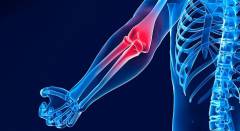

Воспалительный процесс (воспаление) — это реакция организма на повреждение тканей, проявляющаяся отеком, болью, покраснением и нарушением функции. Характер воспаления в локте зависит от причины повреждения и анатомических изменений.

В локте могут воспаляться следующие структуры:

- Локтевой сустав. Воспаление при артритах, остеоартрозе, остеомиелите и синовиальном хондроматозе вызывает боли.

Боли в локте чаще всего связаны с заболеваниями суставных структур, такими как хрящи, кости и суставная капсула. Например, болевые ощущения возникают при артритах, остеоартрозе и пирофосфатной артропатии. Патологии, затрагивающие внесуставные структуры, такие как локтевой бурсит и эпикондилит, также могут вызывать боли.